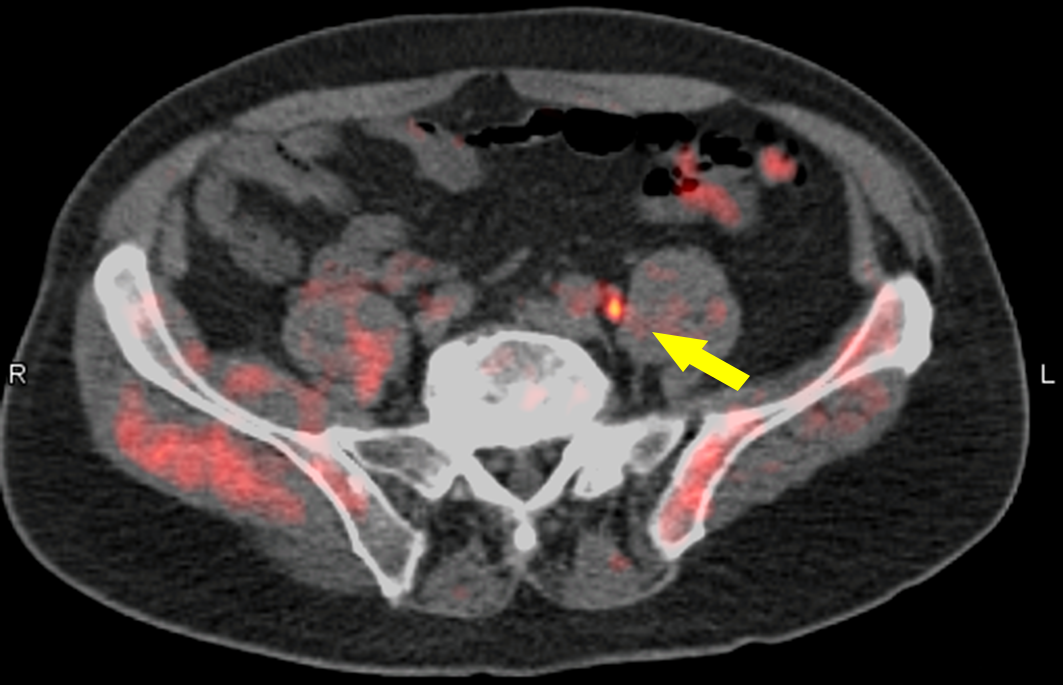

- Imaging studies (CT, PET, MRI) to locate distant sites.

- Biopsy of the metastatic lesion to confirm breast origin and to test receptors (ER, PR, HER2) and genetic mutations (BRCA, PIK3CA).